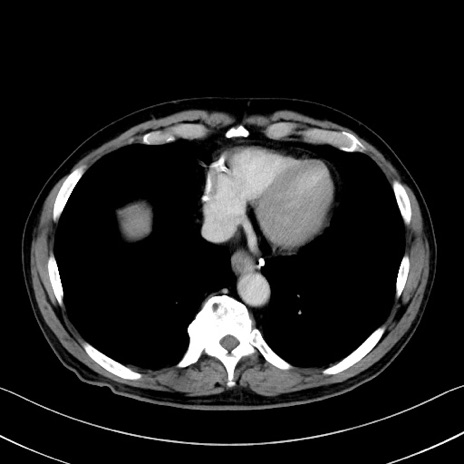

冠状断像